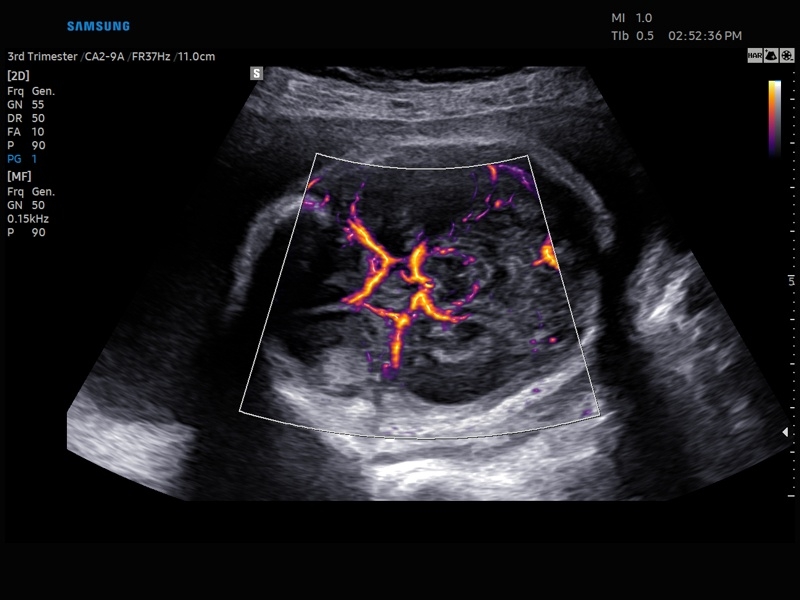

• Модуль5D HeartColor – программа автоматического построения основных срезов средца плода в режиме объемного сканирования с анализом кровотока.

• Модуль Crystal Vue Flow- программа реконструкции прозрачного 3D УЗИ, которое получается при одновременном усилении внутренних и наружных структур. Применяется для визуальной оценки состояния плода и матки, помогает лучше идентифицировать мягкие ткани и кости. Так же визуализирует объемный кровоток.